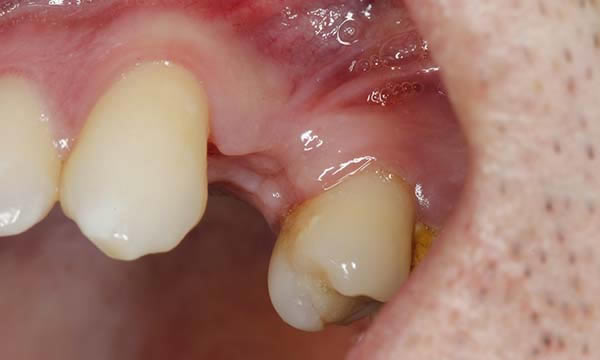

Case B

This gentleman had lost his heavily restored UL4 and decided to close the space with an implant retained crown. The thin buck-palatal width required careful placement to avoid fenestration bucally. A tooth bourn position guide was used to place the implant predictably and within the aesthetic envelope. The implant was restored after three months of osseointegration with a bonded crown.